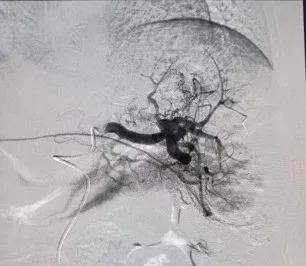

治疗前造影 |

治疗后造影 |

随着医学的发展,传统的外科切除逐步向微创介入治疗演变,而 选择性脾动脉栓塞术 ,具有不开腹,不全麻,术后恢复快等优点,已成为取代脾切除术治疗脾功能亢进的有效治疗方式。

选择性脾动脉栓塞术 是在局麻下在DSA引导下经股动脉穿刺引入导管,插入脾动脉直至脾门部,造影显示脾脏的供血动脉,并经导管向脾动脉内缓慢注射直径为100微米~200微米的微粒进行栓塞即可。不用开刀且安全有效。